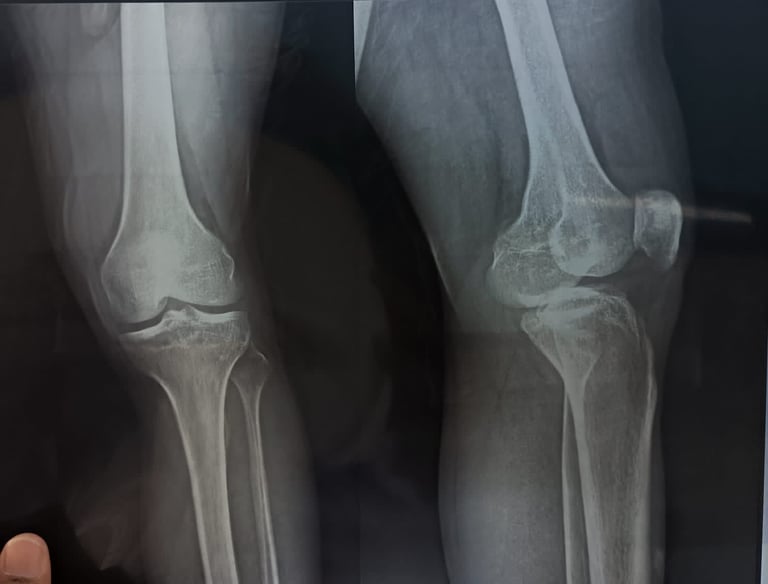

Rheumatic Relief

Gentle treatments easing joint stiffness and pain.